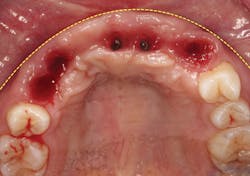

A 21-year-old female was injured five years ago in a jet ski accident. Seven of her maxillary teeth (Nos. 5–11) were avulsed along with the buccal plate. The patient was seen by several specialists to assess treatment options. Ultimately, she was allowed to heal over a few years (figure 1) and given a partial denture in the interim. The patient’s family had many consultations over the years to hear recommendations for restoring her smile with implant-retained crown-and-bridge treatment. At that point in time, options were expensive and the patient was too young to start treatment. The patient wanted fixed maxillary restorations to replace her missing teeth. Treatment began after the patient had graduated from high school and before entering college.

Figure 1: Full retracted view of full bite